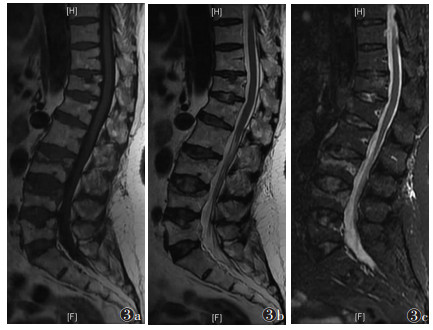

168节椎体中,轻度骨髓水肿32节,中度70节,重度66节。随时间推移,骨髓水肿信号强度逐渐由均匀向非均匀转变,信号范围逐渐减小,边界逐渐清晰;轻度骨髓水肿发生率由8.4%升至50.0%,重度由51.8%降至8.3%,差异均有统计学意义(均P<0.050.05)(表 3)。①Ⅰ期:骨髓水肿比例迅速上升,达到峰值。T1WI、T2WI信号均匀分布,T1WI呈低信号,T2WI和STIR呈高信号,扩散至正常骨髓,呈弥漫性、均匀性、边界不清的形态分布(图 1)。②Ⅱ期:信号分布变得不均匀,水肿范围逐渐受限,并出现点、片状T1WI低信号,T2WI和STIR高信号(图 2)。③Ⅲ期:骨髓水肿较前一期下降,水肿范围局限于骨折区,信号混杂;部分椎体T1WI呈等、低信号,T2WI及STIR呈低、等、高信号(图 3)。④Ⅳ期:骨髓水肿百分比降至最低。T1WI骨折区可见低信号区,边界清晰。T2WI和STIR信号与相邻正常椎体相同(图 4)。

| 图 3 女,69岁,Ⅲ期OVCFs。MRI示骨折位于L3和L4,双凹畸形,MRI示T1WI(图 3a)呈稍低信号,T2WI(图 3b)及STIR(图 3c)均呈稍高信号,矢状位示水肿信号范围缩小至骨折线附近 |